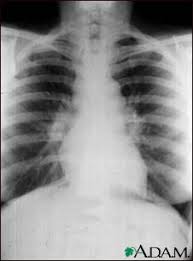

Bedside ECG electrodes and the machine طبعا لأخذ تخطيط اولي للمريض عند دخوله ..